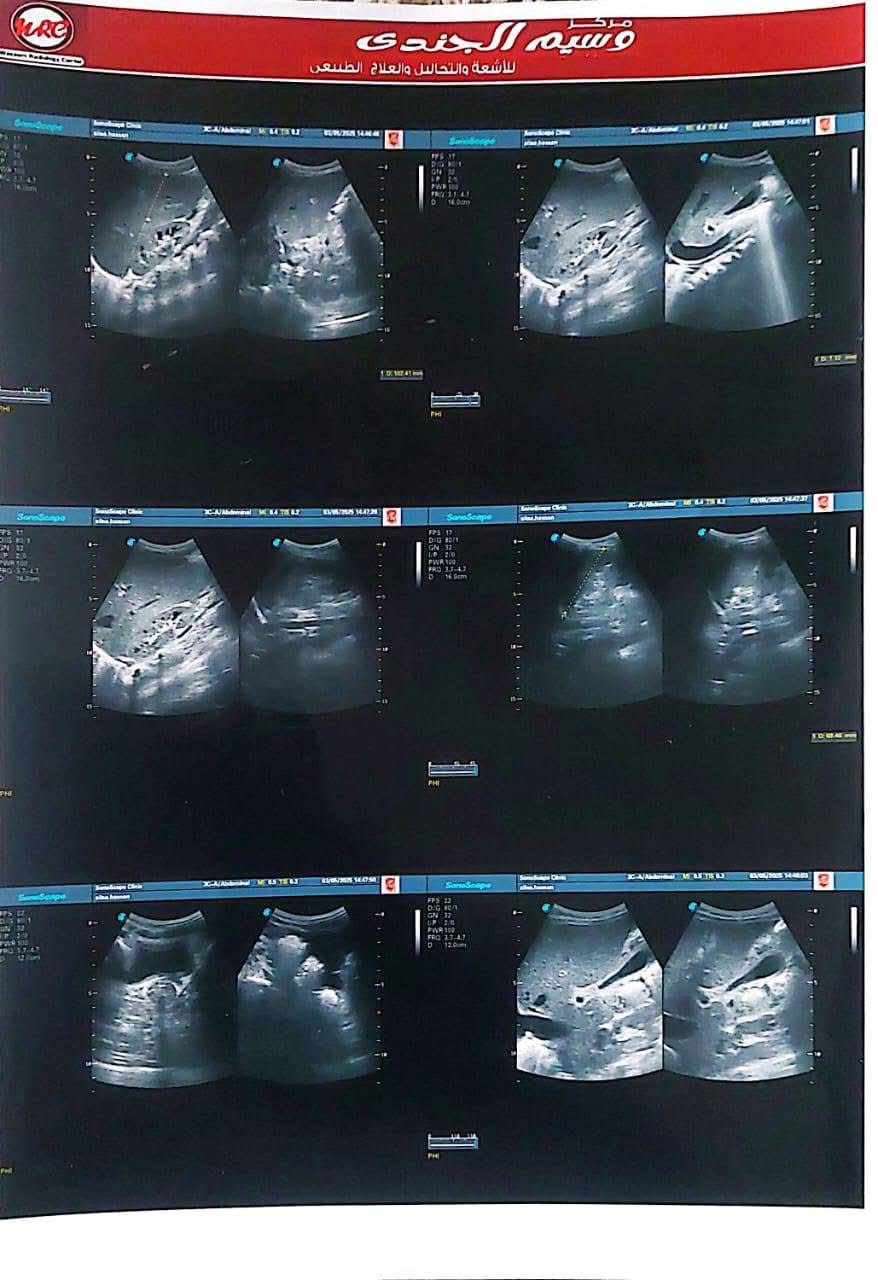

ناشدت أسرة الطفلة عليا حسن، البالغة من العمر أربع سنوات ونصف، الجهات الطبية المعنية وعلى رأسها مؤسسة مجدي يعقوب لأمراض القلب ومستشفى الناس، للتدخل العاجل لإنقاذ حياة ابنتهم، التي تعاني من فشل شديد في عضلة القلب وتضخم كبير بالقلب، ما أدى إلى مضاعفات صحية خطيرة شملت الكبد وأجهزة أخرى من الجسم.

وكشفت أحد أقارب الطفلة تفاصيل الحالة الصحية لها، قائله "عليا حسن بنت خالي 4 سنوات ونصف الأسبوع الماضي جالها استسقاء في معدتها كبير والبنت مكنتش عارفة تتنفس ولا قادرة تتحرك وتعب شديد، لفوا كتير لحد ما عملوا إيكو على القلب وطلع في ضعف شديد في عضلة القلب وتضخم في القلب جامد، ودا طبعا أثر على كل وظائف الجسم وأثر على الكبد بشكل ملحوظ".

وتابعت إحدى أقاربها في منشور لها على الفيسبوك "عليا قعدت في رعاية مستشفى أبو الريش اسبوع، لحد ما كفاءة القلب وصلت ٢٠٪، الحد الأدنى لعمرها ٥٥٪، وخرجت الحمد لله، بس الدكاترة قالوا محتاجة تدخل جراحي سريع لأن حالتها حرجة جدا، محتاجة زرع قلب".